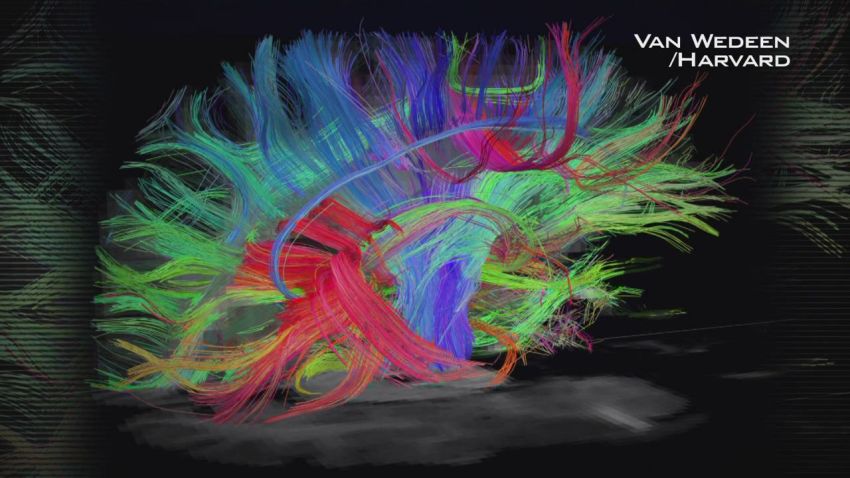

Коннектом мозга: визуализация связей и нейронных путей